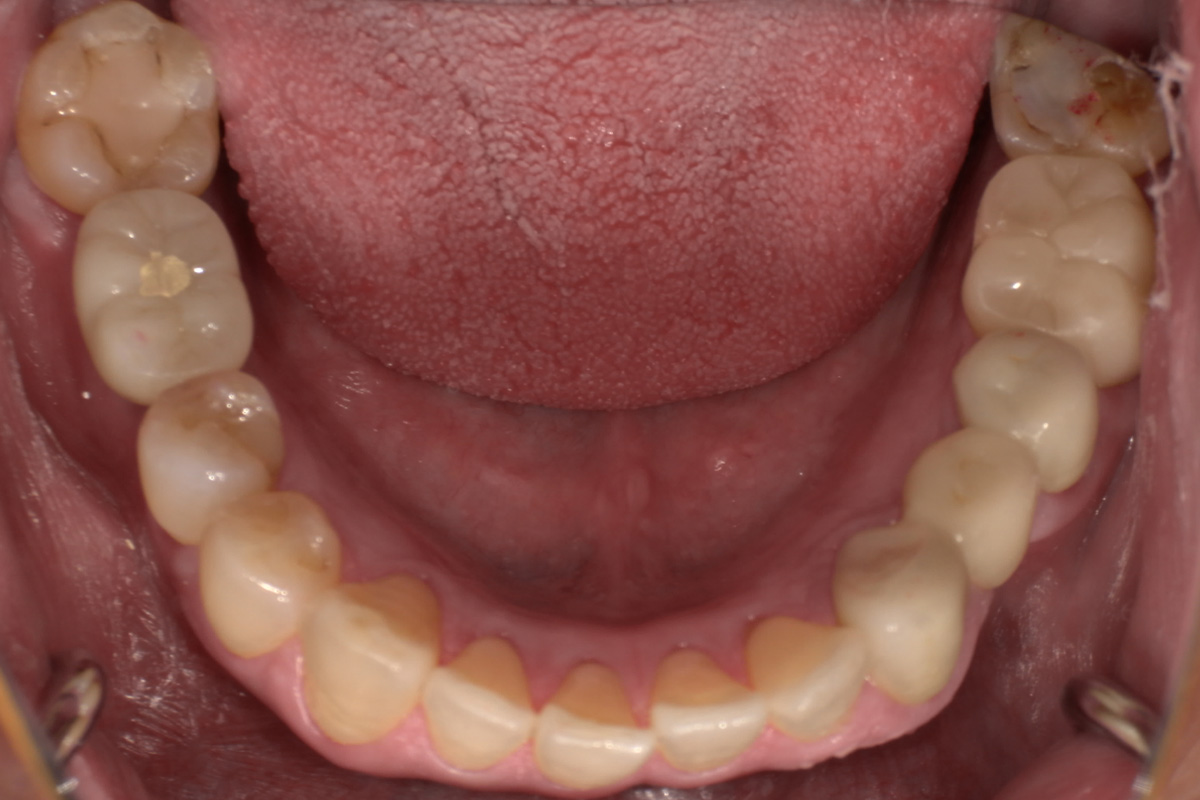

抜歯した箇所にインプラント治療を行った例

術前・術後の比較

初診時

歯が割れていて、痛みがあり、抜歯となりました。

パノラマレントゲン写真 -

インプラント手術から3ヵ月後、型どりをして、仮歯を製作しました。

仮歯の調整期間を経て、セラミックの歯が入りました。

レントゲン画像 治療前 インプラント治療後